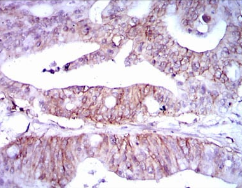

Immunogen:    Purified recombinant fragment of human LPA (AA: 1823-2013) expressed in E. Coli.

IHC    1/200 - 1/1000